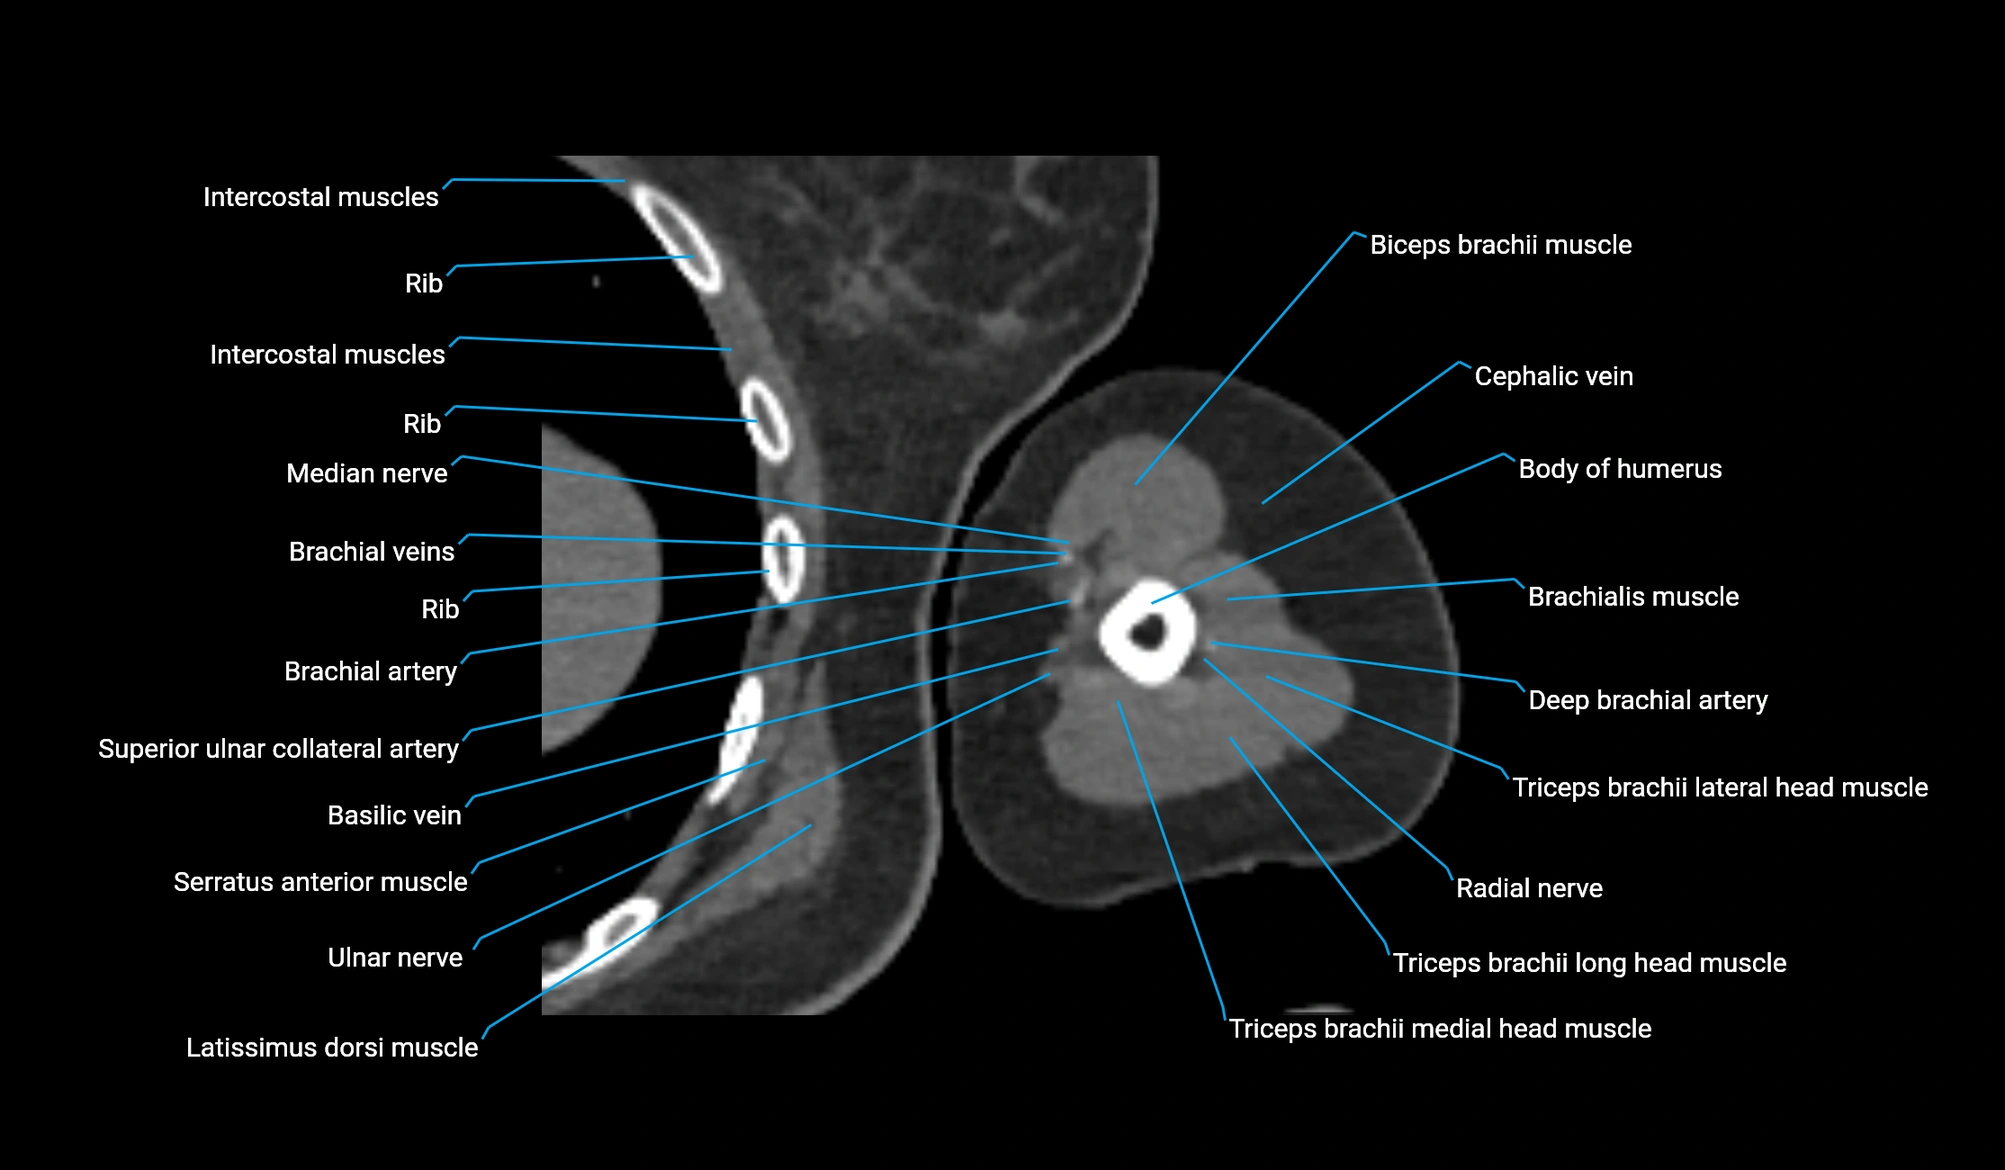

CT image